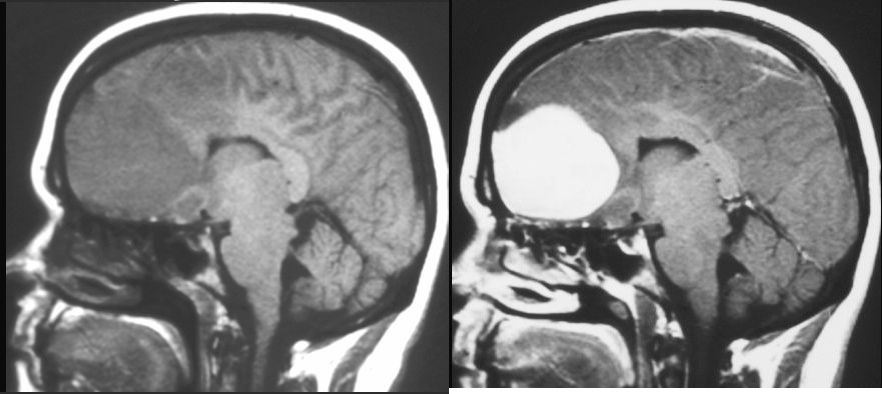

OPONIAK

MRI